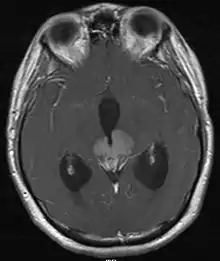

Le diagnostic repose en premier lieu sur l'IRM du cerveau, puis le type histologique[8] de la tumeur est précisé par une biopsie stéréotaxique, réalisée par un neurochirurgien. On profite généralement de cette opération pour réaliser, en plus une ventriculocisternostomie[8], pour permettre l'écoulement du liquide cérébro-spinal, ou liquide céphalo-rachidien en ancienne nomenclature. Ce geste est essentiel pour réduire l'HTIC, qui demeure une urgence médico-chirurgicale.